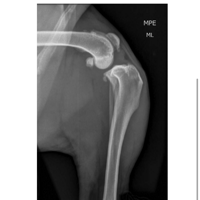

Olá pessoal me chamo Aline, e sou a dona do Blake um American bully de 3 anos que rompeu o ligamento das duas patas, onde é necessário uma cirurgia, o mesmo foi encaminhado a um hospital veterinário público, porém como a cirurgia é de grande porte e custo o governo não libera esse procedimento, sendo assim somente pode ser realizado em clínicas particulares, e eu no momento não tenho condições de arca com esse valor todo, quem puder estar ajudando com 1 real que seja já é de grande ajuda, vamos ajudar ele a fazer essa cirurgia e ficar bem, des de já agradeço a todos.